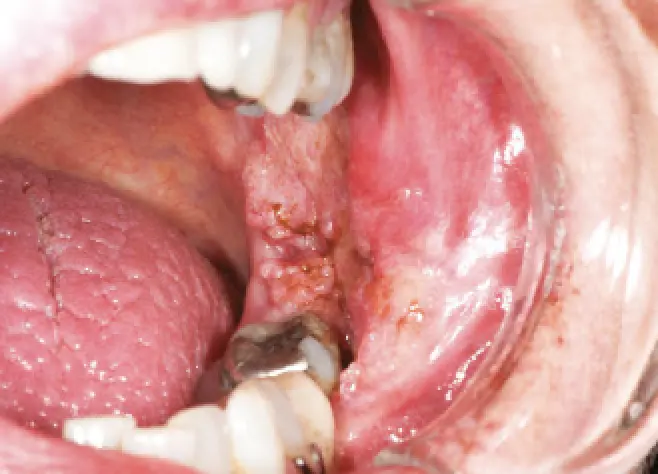

Oral squamous cell carcinoma (SCC) is the most common oral malignancy and typically presents:

- as a non-healing ulcer

- with indurated, rolled edges

- often on the lateral tongue or floor of mouth

Image 2: SCC of the left buccal/retromolar trigone region (source: https://www1.racgp.org.au/ajgp/2020/september/common-benign-and-malignant-oral-mucosal-disease)